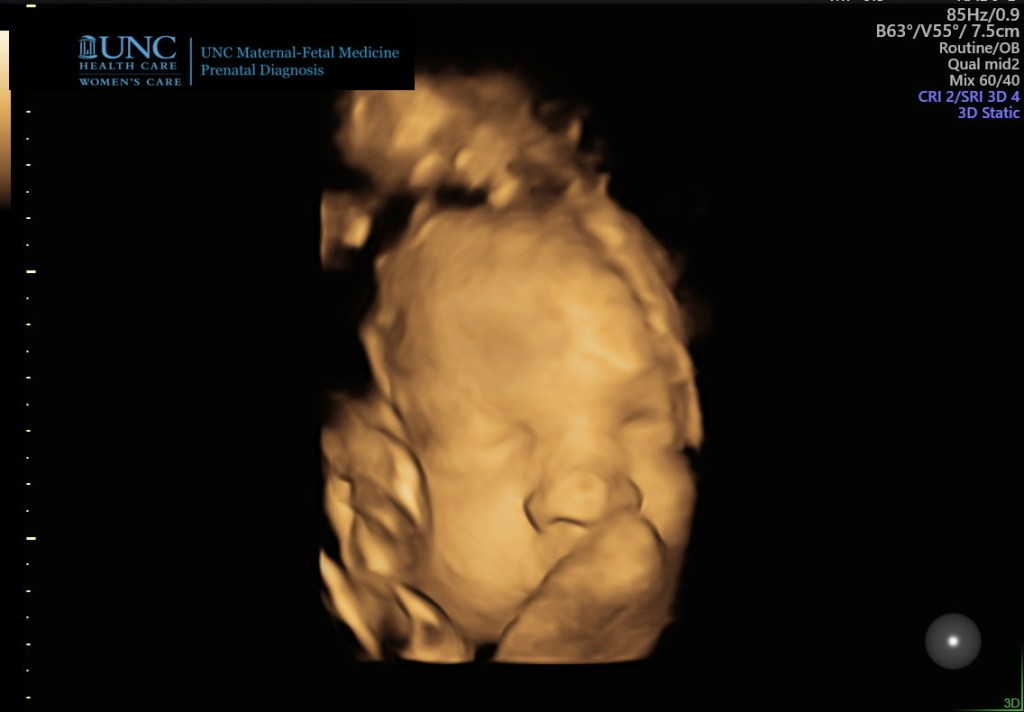

At the ultrasound last week, we got to see Chet’s cute little face again! He has continued growing, and they estimate he is 5lbs now! But they also detected a slight excess of amniotic fluid. The doctors proceeded to list several issues that could cause this. Then they said none of those issues were possible in my case based off of previous test results. They said there may be nothing wrong and I may have extra fluid for no known reason. They recommended close monitoring, as we are already doing.